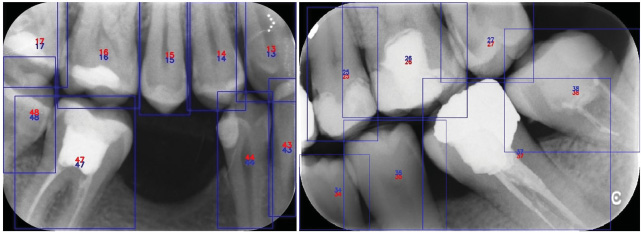

The deep CNN system showed promise for numbering teeth in bite-wing radiographs (Figures 4 and 5). The sensitivity and precision were high for numbering and detecting teeth. The sensitivity, precision and F-measure values were 0.9748, 0.9293 and 0.9515, respectively (Tables 1 and 2). Of the 108 radiographs that constituted the test group, 96 (88.9%) did not have a tooth deficiency, and 12 (11.1%) had a tooth deficiency. The number of missing teeth in these radiographs was 15.

Figure 4. The numbering of teeth in bite-wing radiographs using a deep convolutional neural network system

Figure 5. The numbering of missing and restored teeth in bite-wing radiographs using a deep convolutional neural network system